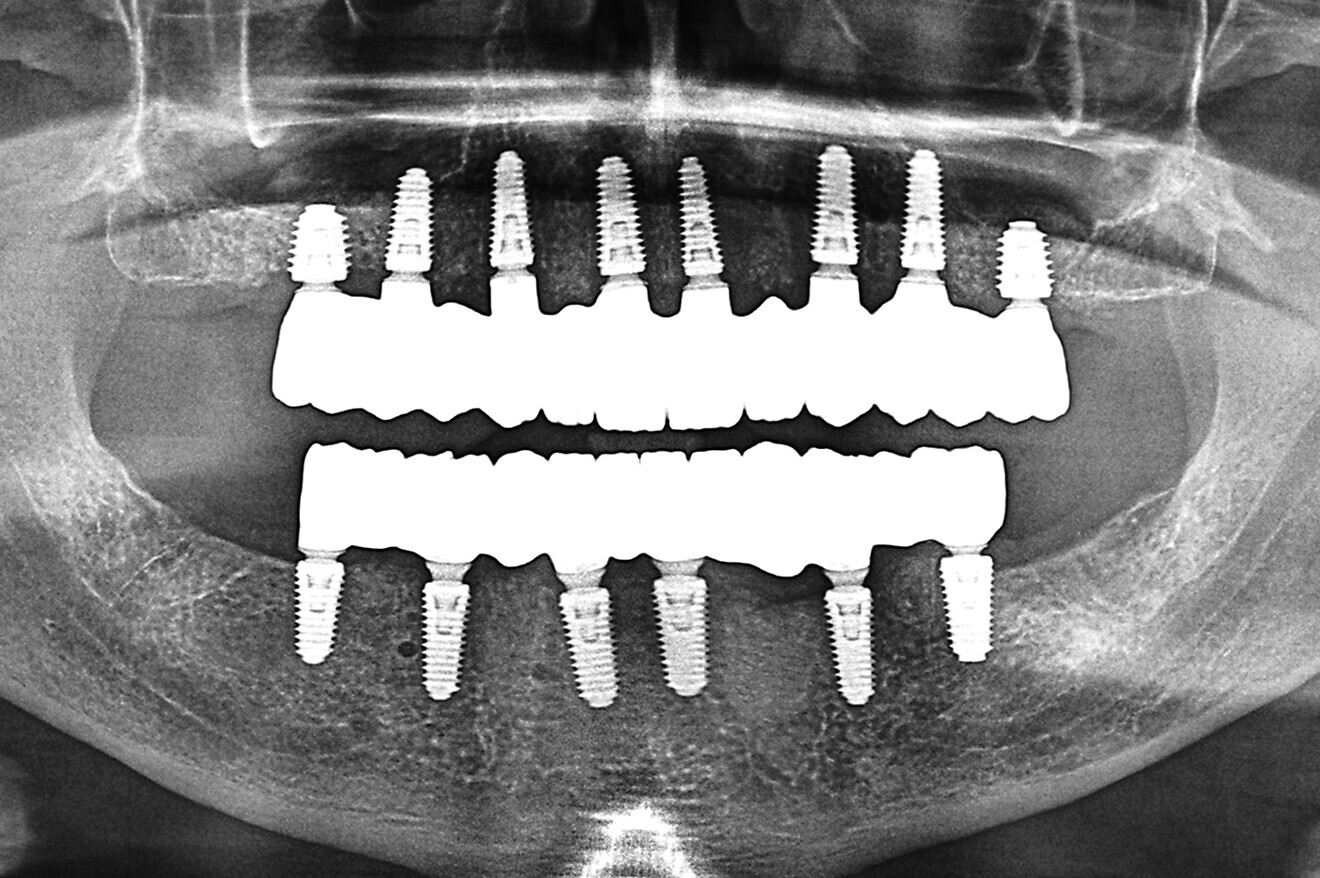

Fig. 17a: Final panoramic radiograph confirming seating of the zirconia restorations.

The data collected was sent through a scanning software portal (Medit Scan for Clinics) to the dental laboratory with requested changes for correction of the desired smile design. Utilising advanced planning features in the design software (exocad), the midline and tooth size changes were corrected. 3D-printed maxillary and mandibular PMMA restorations were used for try-in using the direct-to-MUA screws (Vortex LA VIS; Fig. 16a). Fit, phonetics, aesthetics and occlusion were evaluated and confirmed using digital articulation (OccluSense; Fig. 16b). The patient was extremely satisfied with the printed try-ins. Since no adjustments were required, the patient was allowed to leave with the printed try-ins as new provisional restorations made from extra-strong resin. The new provisional restorations were worn for ten days to confirm form and function. The final shade was chosen, and metal-free monolithic zirconia restorations were then fabricated by the laboratory.

The final restorations were passively and accurately seated ten days later uneventfully using Vortex LA VIS screws. Confirmation records were taken with photographs, radiographs and digital articulation to recheck fit, function, phonetics and occlusion (Fig. 17a). The patient was extremely satisfied with his final restorations, describing the process as life-changing and surprisingly fast in comparison with what he had heard about full-mouth implant therapy. He was especially pleased with the speed at which the final process was able to be completed (Figs. 17b & c).